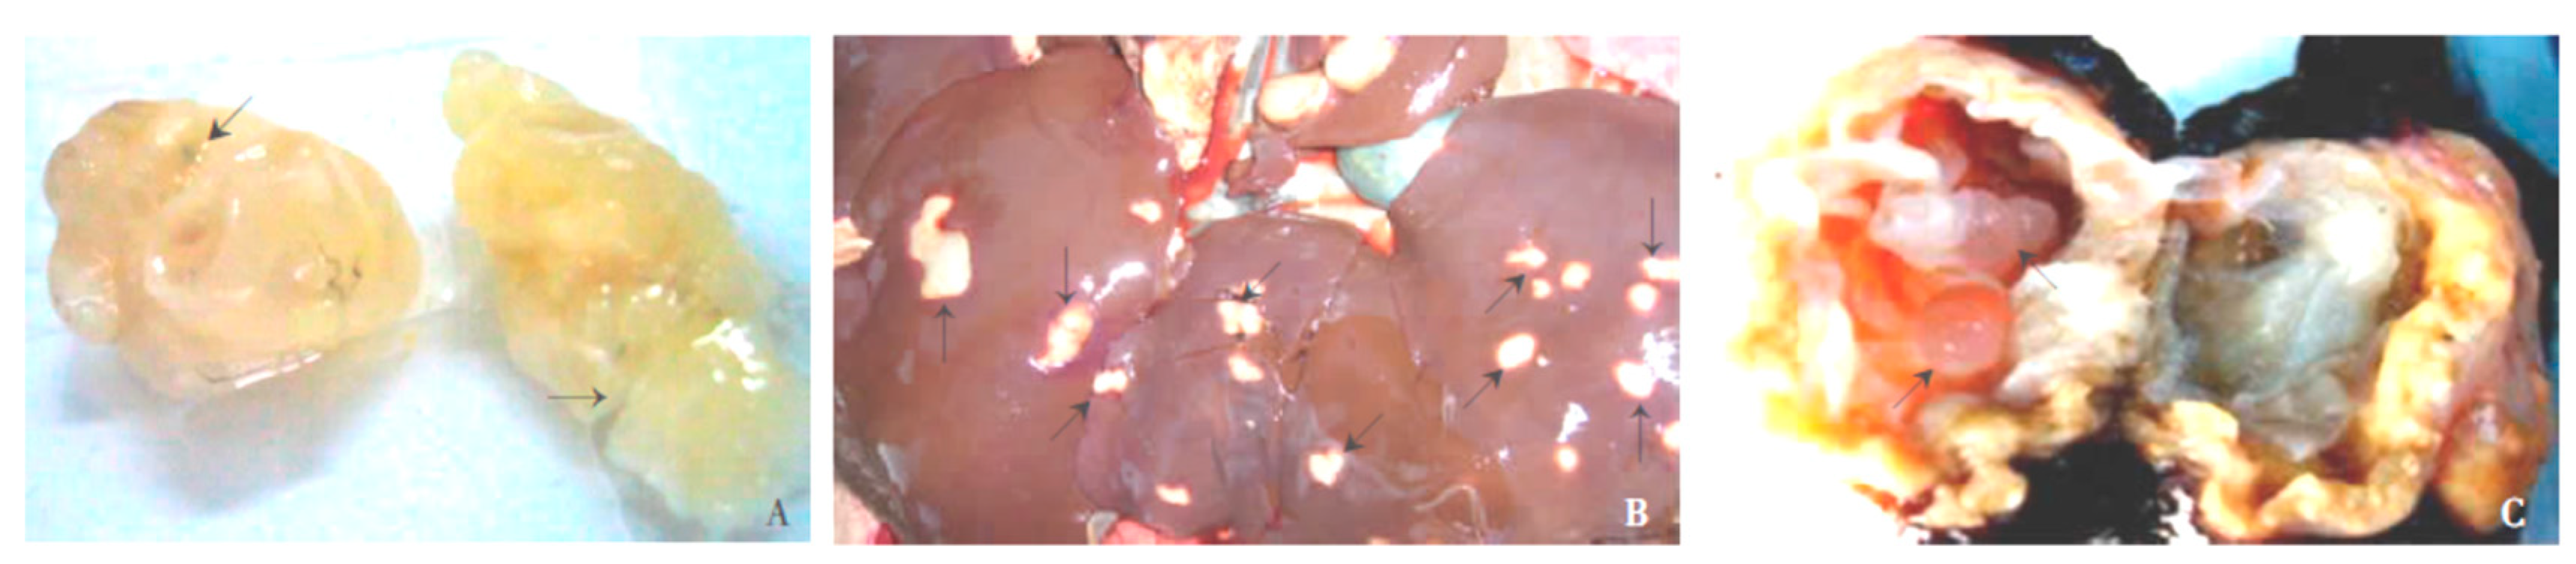

- Liu, Y.; Abudounnasier, G.; Zhang, T.; Liu, X.; Wang, Q.; Yan, Y.; Ding, J.; Wen, H.; Yimiti, D.; Ma, X. Increased Expression of TGF-beta1 in Correlation with Liver Fibrosis during Echinococcus granulosus Infection in Mice. Korean J. Parasitol. 2016, 54, 519–525. [Google Scholar] [CrossRef] [PubMed]

- Labsi, M.; Soufli, I.; Khelifi, L.; Amir, Z.C.; Touil-Boukoffa, C. In vivo treatment with IL-17A attenuates hydatid cyst growth and liver fibrogenesis in an experimental model of echinococcosis. Acta Trop. 2018, 181, 6–10. [Google Scholar] [CrossRef]